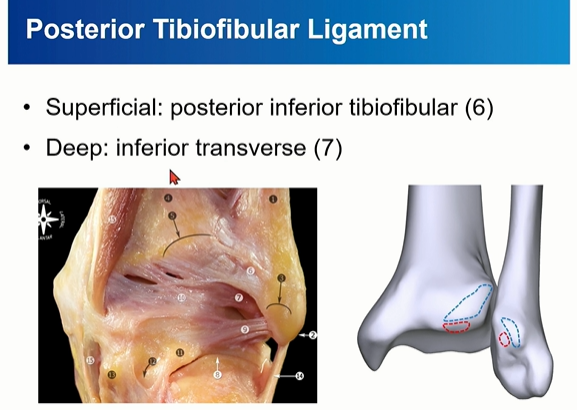

PITFL 은 superfical component와 deep component로 구성되는데, deep component를 inferior transverse ligament라고 부름.

4-3. PITFL

PITFL 은 superfical component와 deep component로 구성된다.

deep component를 inferior transverse ligament라고 부름. 이름대로 horizontal 하게 주행하는 것을 확인할 수 있다.

PITFL은 superficial 과 Deep으로 나누어 보기도 한다.

빨간색으로 표시된 inferior transverse ligament가 아래 쪽에서 주행하는 것을 확인할 수 있다.

파란색으로 표시한 posterior inferior tibiofibular ligment는 위쪽에서 oblique하게 주행하는 것을 확인할 수 있다.